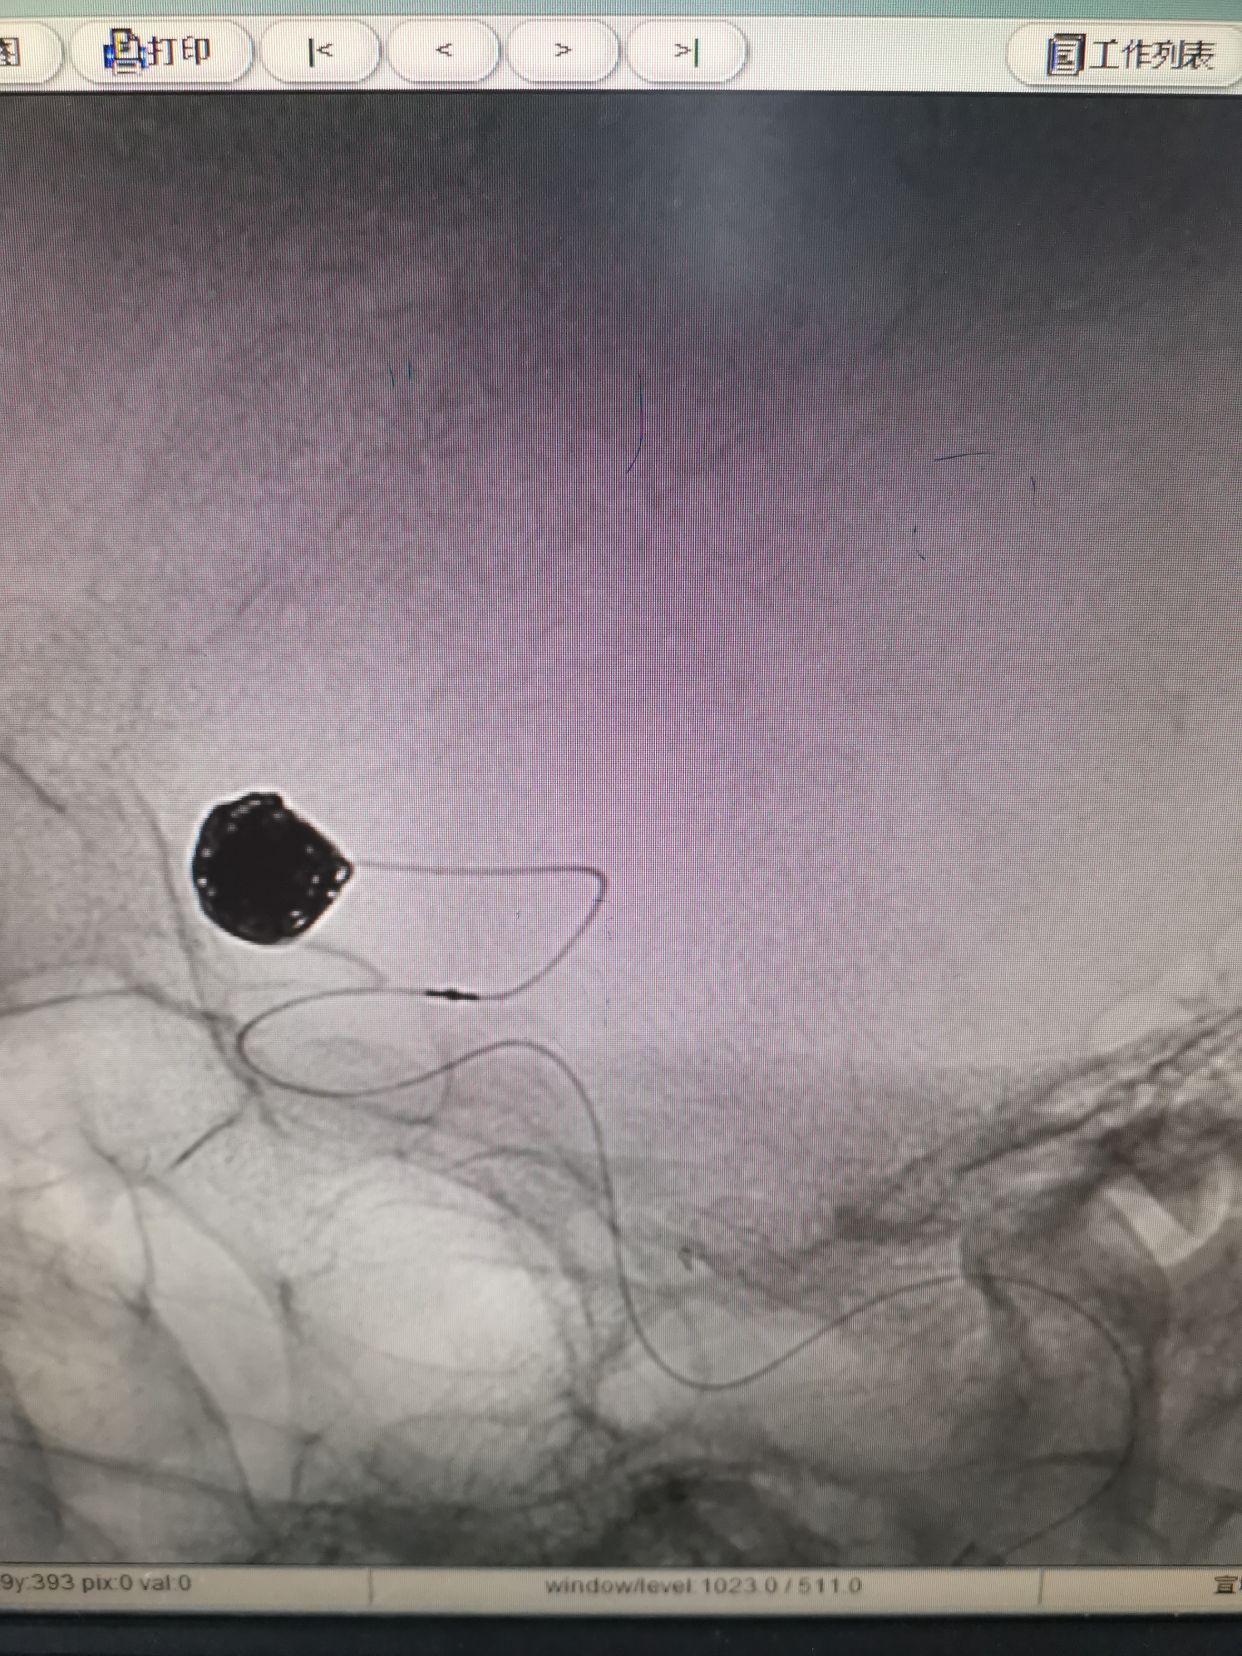

微导管到位后,填入Cosmos Complex 7mm/22cm

继续填入Complex 6mm/26cm

继续填入Complex 6mm/18cm

继续填入Complex 5mm/15cm

术后动脉瘤不显影,双侧大脑前显影。右侧略差。